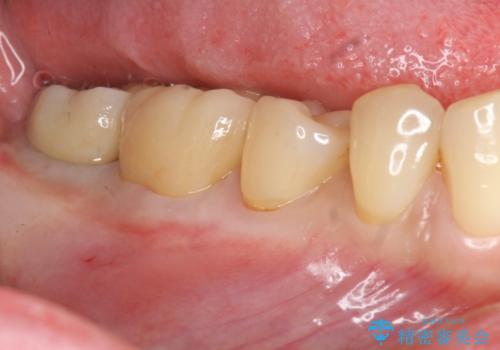

抜歯時歯槽堤保存術を用いた骨造成・インプラント治療

- 50万円(ストローマンインプラント・骨造成・チタンカスタムアバットメント・ジルコニアクラウン)費用は治療当時の料金となります